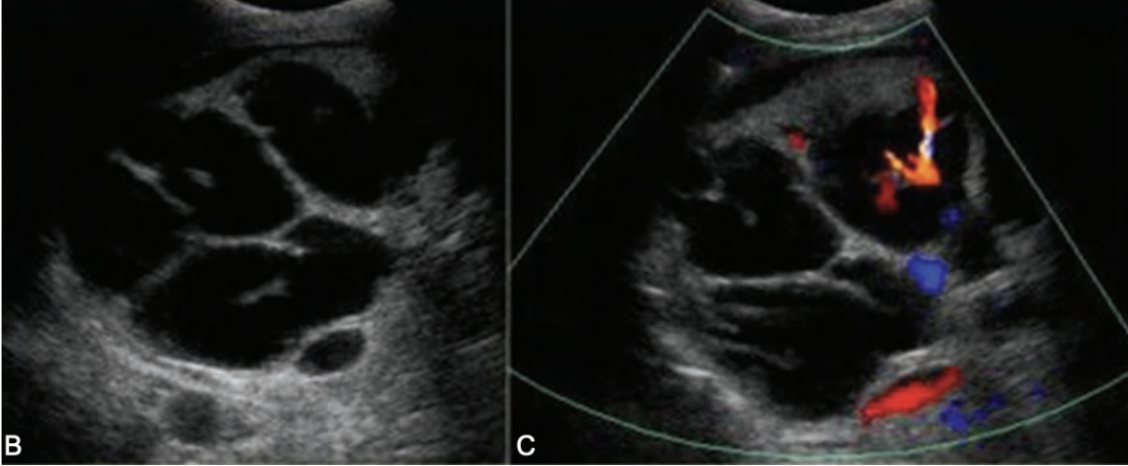

SONO: Caroli’s disease

multiple cystic structures in the track of ducts (in the area of the ductal system) that converge at portal hepatitis

“Central dot” sign = dilated duct surrounding the adjacent HA and PV

one Mickey ear is bigger than the other

??

Type 5 choledochal cysts (Caroli’s disease)